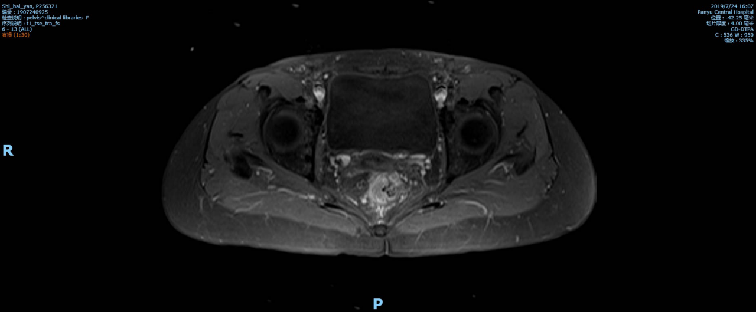

2019-10-09复查盆腔MR示直肠全段管壁不均匀增厚,以中段较明显,最厚处约11mm,较前相仿,仍考虑直肠癌累及浆膜面,较前略有好转,不除外直肠前筋膜受累;胸腹CT未见转移征象。

术前影像学检查: